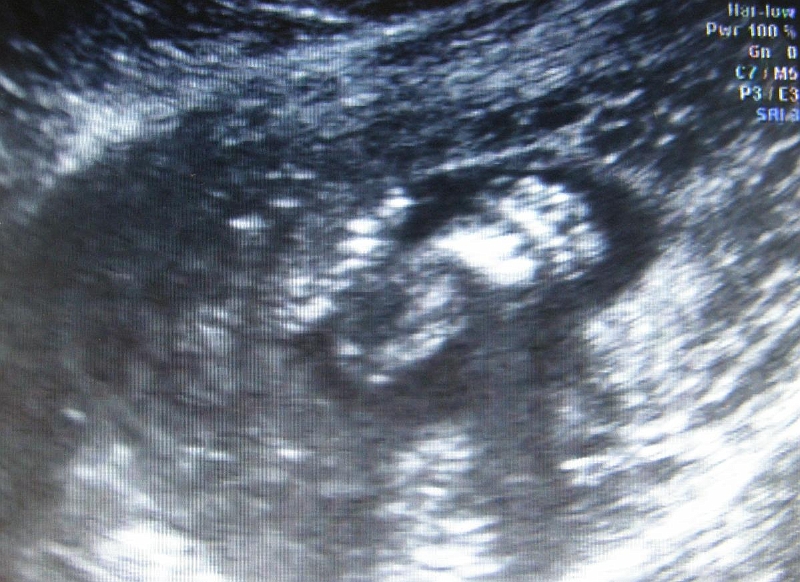

kregoslup serce zoladek